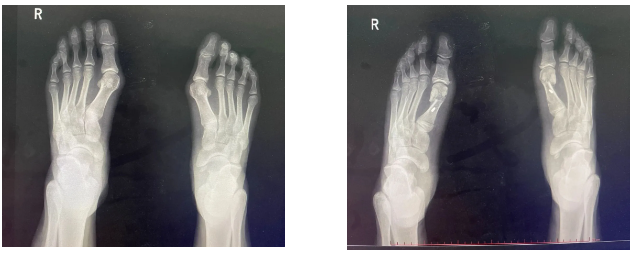

然而,当踇外翻发展到较为严重的程度,保守治疗效果不佳时,手术治疗就成为必要的选择。手术的目的是纠正趾的畸形,恢复足部的正常结构和功能。目前有多种手术方法可供选择,如截骨术、软组织手术等。截骨术主要是针对骨骼结构的改变,通过对第一骨等相关骨骼进行切割、重新定位和固定,来调整趾的力线。而软组织手术则侧重于对趾周围的韧带、肌肉等软组织进行修复和调整。手术治疗需要根据患者的具体情况,如年龄、健康状况、踇外翻的严重程度等因素进行综合评估,选择较为适合的手术方案。